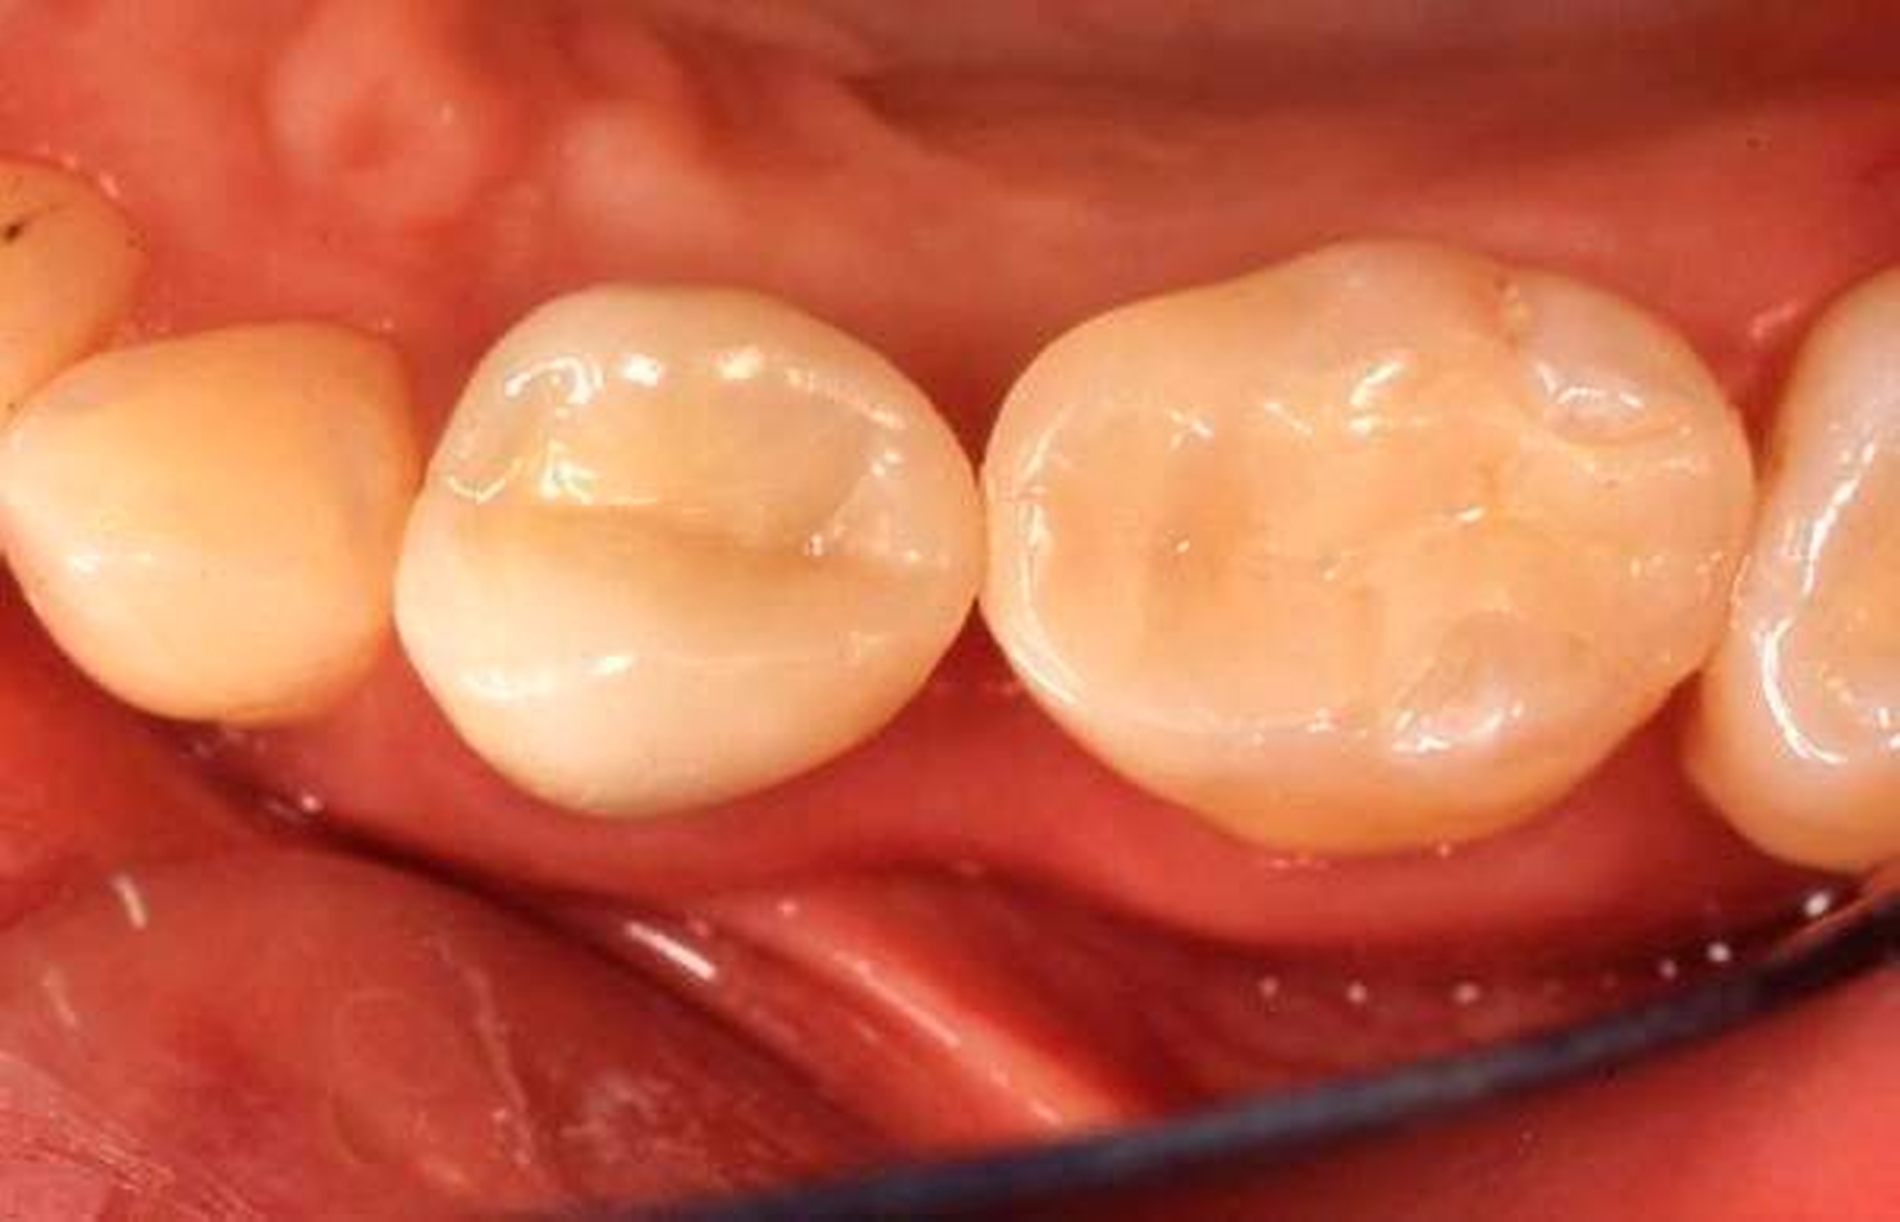

Abbildung 3: Direkte Reparatur im Seitenzahnbereich (R2-Technik)

In den Abbildungen 1 bis 3 werden Optionen für frugale Interventionen auf restaurativem Sektor aufgeführt. Es handelt sich um direkte Vollüberkronungen im Frontzahnbereich (hier: hergestellt in R1-Technik / einphasig) (Abbildung 1), direkte Teilüberkronungen im Seitenzahnbereich (hier: hergestellt in R1-Technik / einphasig) (Abbildung 2), Reparatur-Restaurationen im Seitenzahnbereich (hier: hergestellt in R2-Technik / zweiphasig) (Abbildung 3). Technische Einzelheiten zur Vorgehensweise und den Ergebnissen sind an anderer Stelle beschrieben (Literatur siehe oben).

schadensgerechte Reparaturtechniken (Abbildung 3),